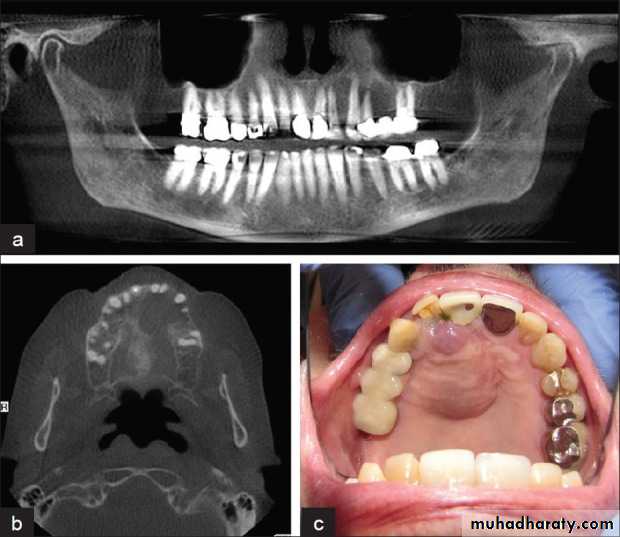

Squamous cell carcinoma

Squamous cell carcinomas of the oral mucosa directly overlying bone, in their latter stages, often invade the underlying bone to produce a destructive radiolucency.• Age: Adults over 50 years old.

• Site: Mandible, or maxilla if originating in the antrum.

Shape: Irregular area of bone destruction often initially saucer-shaped.

Outline: — Irregular and moth-eaten

— Poorly defined

— Not corticated.

Radiodensity: Radiolucent, radiodensity dependent on degree of destruction.